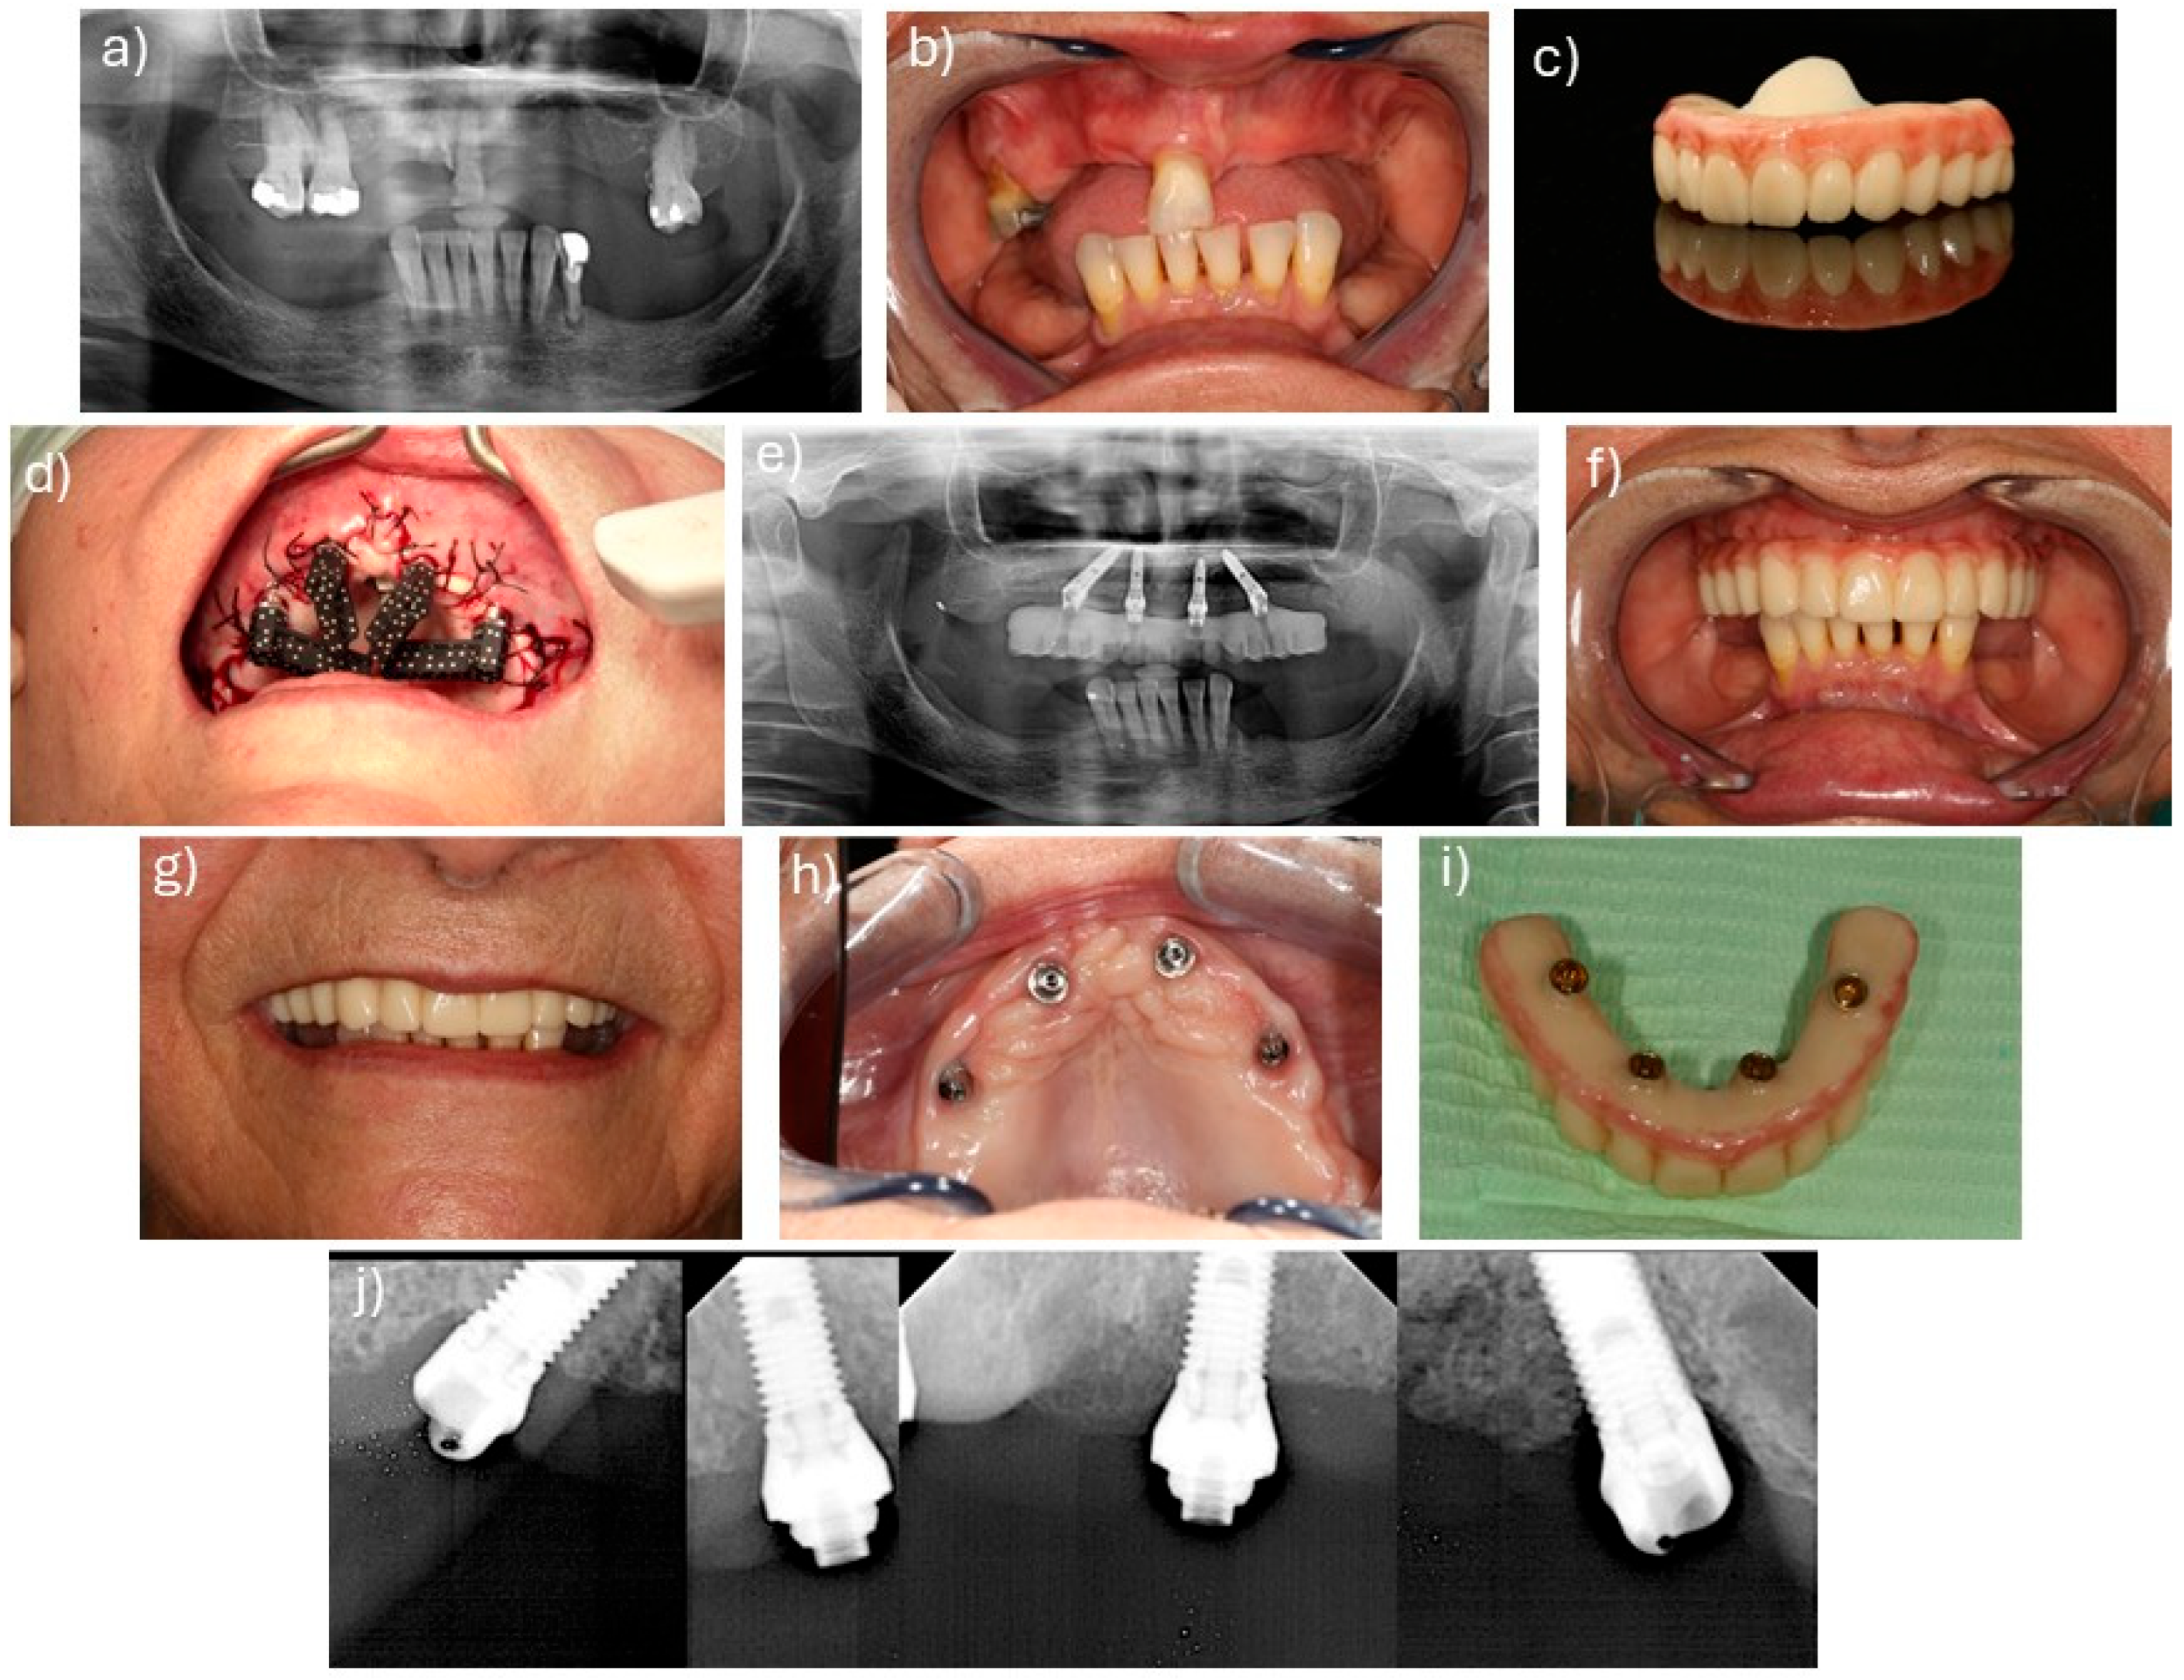

2.2. Surgical and Prosthetic Protocols